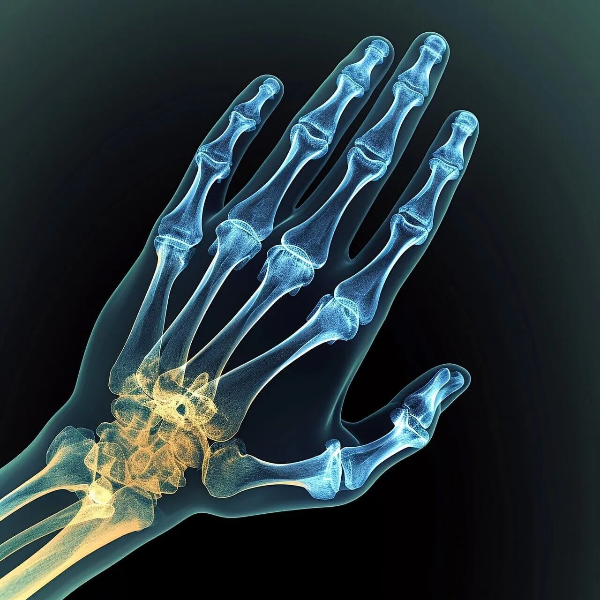

뼈 밀도가 서서히 줄어들고,

구조가 약해져도

몸은 거의 신호를 보내지 않습니다.